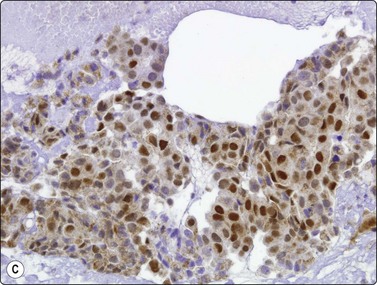

image image image

Fig. 8.35 Carcinoid tumor, spindle cell type

Tight aggregate of spindle cells with little pleomorphism. Cell block showing no mitotic activity or necrosis. Strong positive immunostaining for synaptophysin (A, H&E, HP; B, Cell block, H&E, HP; C, Cell block, IPOX, HP).

In ‘classic’ carcinoid tumors, the FNB findings are often distinctive enough to permit diagnosis, with or without ancillary tests such as immunocytochemistry. In contrast, the atypical carcinoids that we have seen were more difficult to classify before resection. Nicholson et al. found similar problems in recognizing a proportion of their neuroendocrine carcinomas, including low- and high-grade tumors, and suggested that ‘attention to the presence of loose cell aggregates in a background of singly dispersed cells; feathery patterns created by tumor cells clinging to capillaries; rosette formations; delicate, granular cytoplasm; inconspicuous nucleoli; molding in high-grade tumors; and, most importantly, speckled or dusty chromatin patterns are useful in identifying neuroendocrine differentiation in cytologic specimens’.36